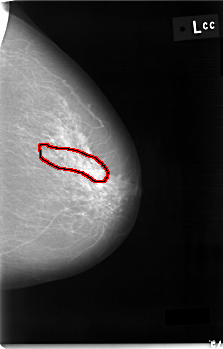

FILE: C_0002_1.LEFT_CC.OVERLAY

TOTAL_ABNORMALITIES 1

ABNORMALITY 1

LESION_TYPE CALCIFICATION TYPE PLEOMORPHIC DISTRIBUTION SEGMENTAL

ASSESSMENT 4

SUBTLETY 2

PATHOLOGY MALIGNANT

TOTAL_OUTLINES 1

BOUNDARY